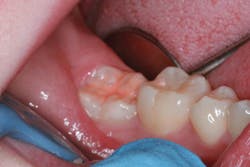

Photo courtesy of Dr. Daniel H. Ward, Columbus, OH

Decisions about sealant use should be based on the best available evidence about the effectiveness of the intervention on dental caries, including the risk factors and the epidemiology (Beauchamp). Clinicians should incorporate the science with the patient's individual needs and preferences. The oral health considerations of the patient include dry mouth, ability to perform oral care, caries risk, etc., giving the clinician a good understanding of which candidates should have sealants placed. Limiting the placement of sealants to only children and adolescents can limit preventive measures for adults and seniors.